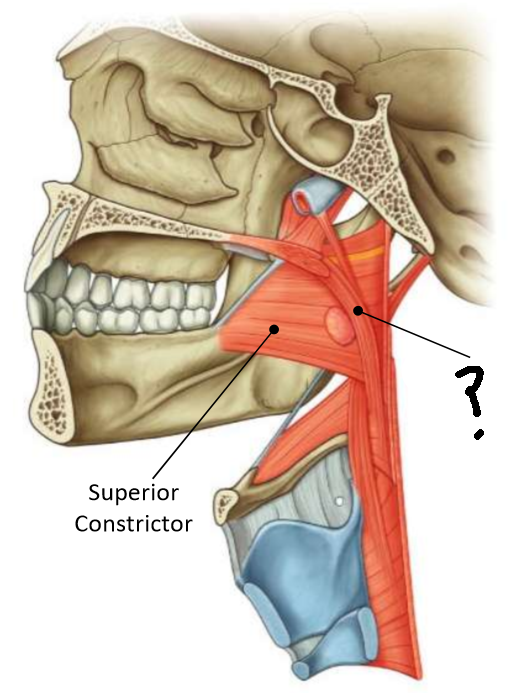

What muscle is this?

superior constrictor

What is the upper border of this muscle?

palatopharyngeal sphincter

What is 1?

pterygomandibular raphe

What is 2?

stylohyoid ligament

What are the attachments of this muscle?

pterygoid hamulus, pterygomandibular raphe, posterior end of mylohyoid line → pharyngeal raphe